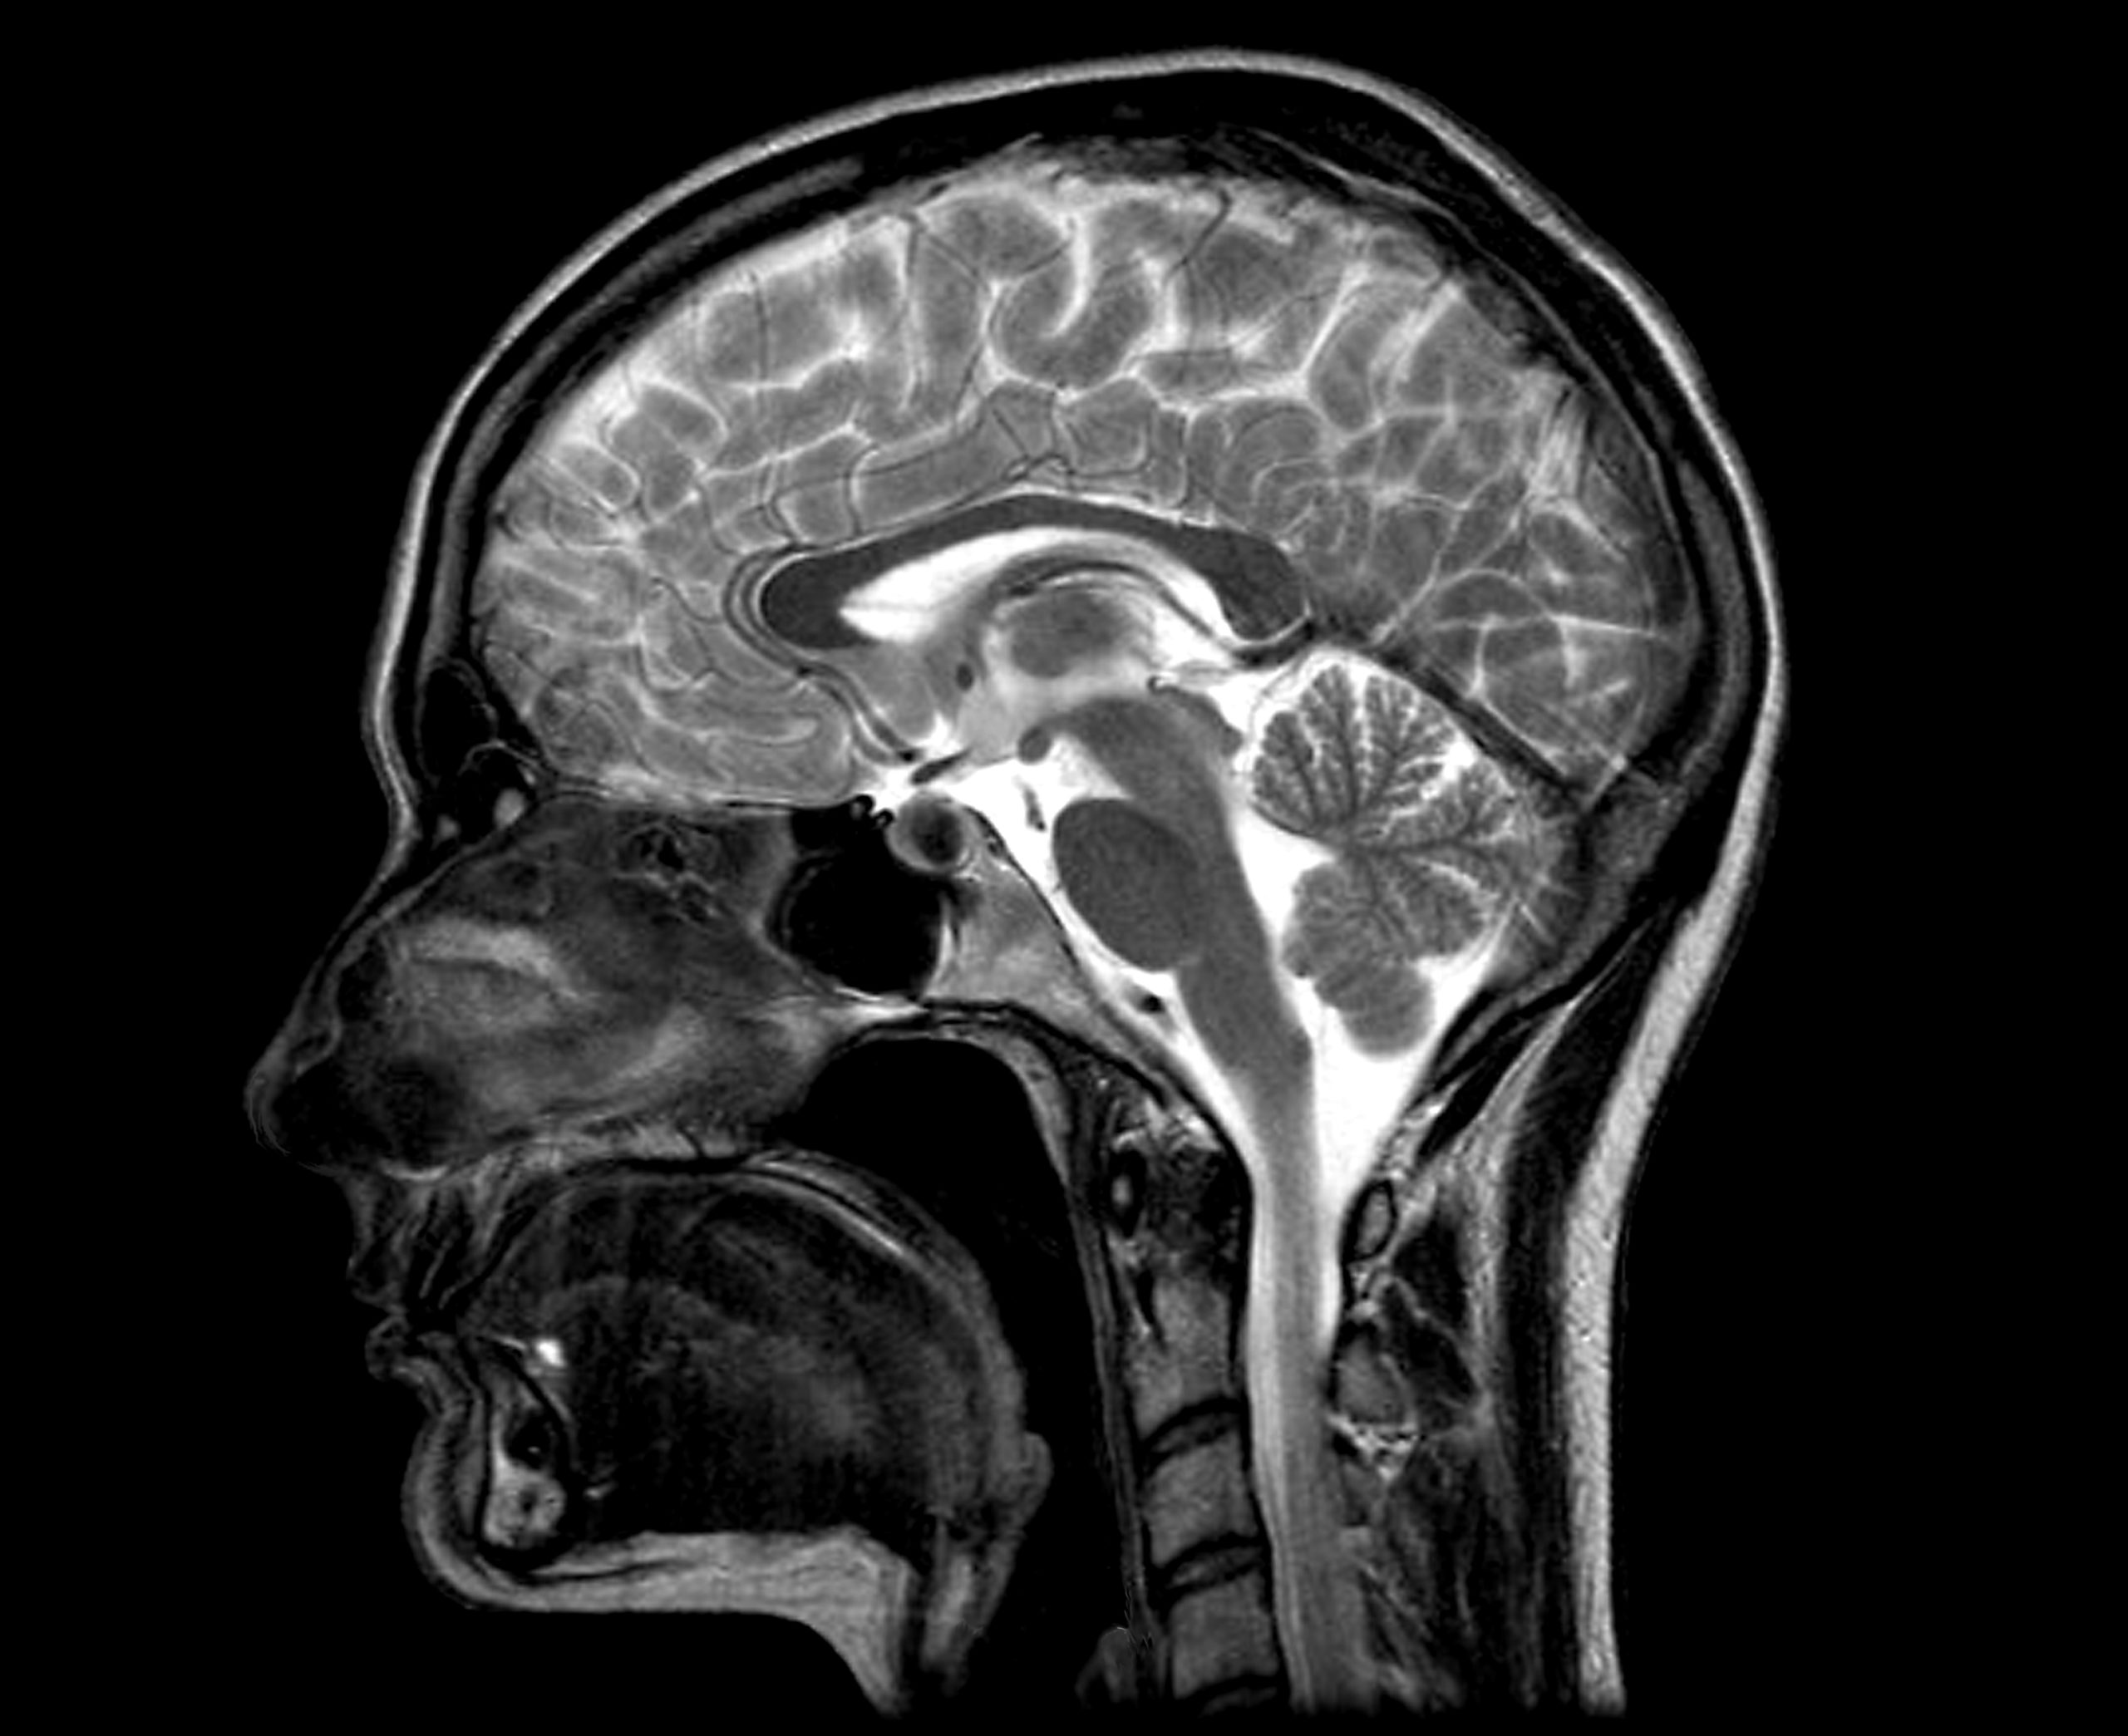

Should Everyone Get a CT Scan After a Head Injury? Premier Neurology

From premierneurologycenter.com

Should Everyone Get a CT Scan After a Head Injury? Premier Neurology Markers For Brain Injury Markers identifiable through neuroimaging, proteins that can be measured in blood. To inform future guideline formulation, it is critical to distinguish between. Glial fibrillary acidic protein (gfap), s100, and neurons specific enolase (nse) were the most prominent and frequently cited markers. Flow diagram of the different types of tbi biomarkers that denote many processes such as neuronal injury, glial injury,. Markers For Brain Injury.